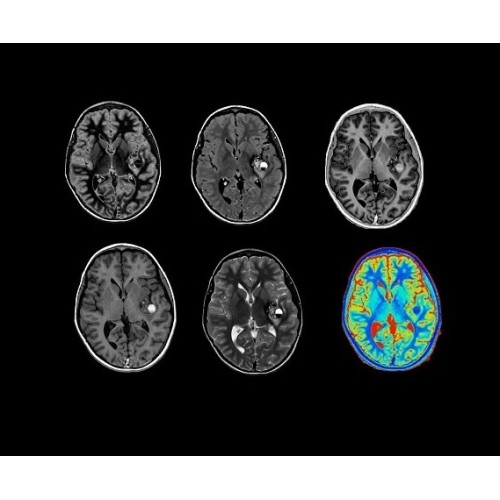

SIGNA PET/MR 3.0T — это гибридная система, в которой совмещаются две принципиально разные технологии — магнитно-резонансную томографию (МРТ) и позитронно-эмиссионную томографию (ПЭТ). Система отличающийся высокой чувствительностью и эффективностью и предназначена для диагностики в области онкологии, неврологии, кардио-васкулярных исследований, исследований воспалительных процессов.

Компания GE Healthcare представляет революционную, полностью интегрированную систему SIGNA PET/MR1, в которой сочетаются времяпролетная технология (TOF) и возможности напряженности магнитного поля 3.0 Тл. Мы поможем вам поднять исследования на более высокий уровень. SIGNA PET/MR позволяет достичь впечатляющей точности и скорости исследований, а благодаря новейшей технологии реконструкции Q.Clear2 качество изображений улучшается в два раза. Кроме того, в систему включен полный набор клинических приложений и гибких катушек для проведения любых видов исследования, открывая для вас возможности визуализации, о которых вы даже не догадывались.

• Q.Clear — в основу технологии легли накопленные знания о том, как минимизировать помехи при реконструкции и получить четкое изображение. При значительном улучшении качества изображения сохраняется точность расчетов. Сочетание технологии TOF и реконструкции Q.Clear — ваш надежный помощник для получения точных и достоверных данных.

• Специальный пакет приложений для измерения и сравнения объемных изображений ЦНС с нормами поможет вам в диагностике нейродегенеративных заболеваний, а дополнительные инструменты визуализации — в постановке точного диагноза с помощью бета-амилоидов и радиоизотопных маркеров ФДГ.